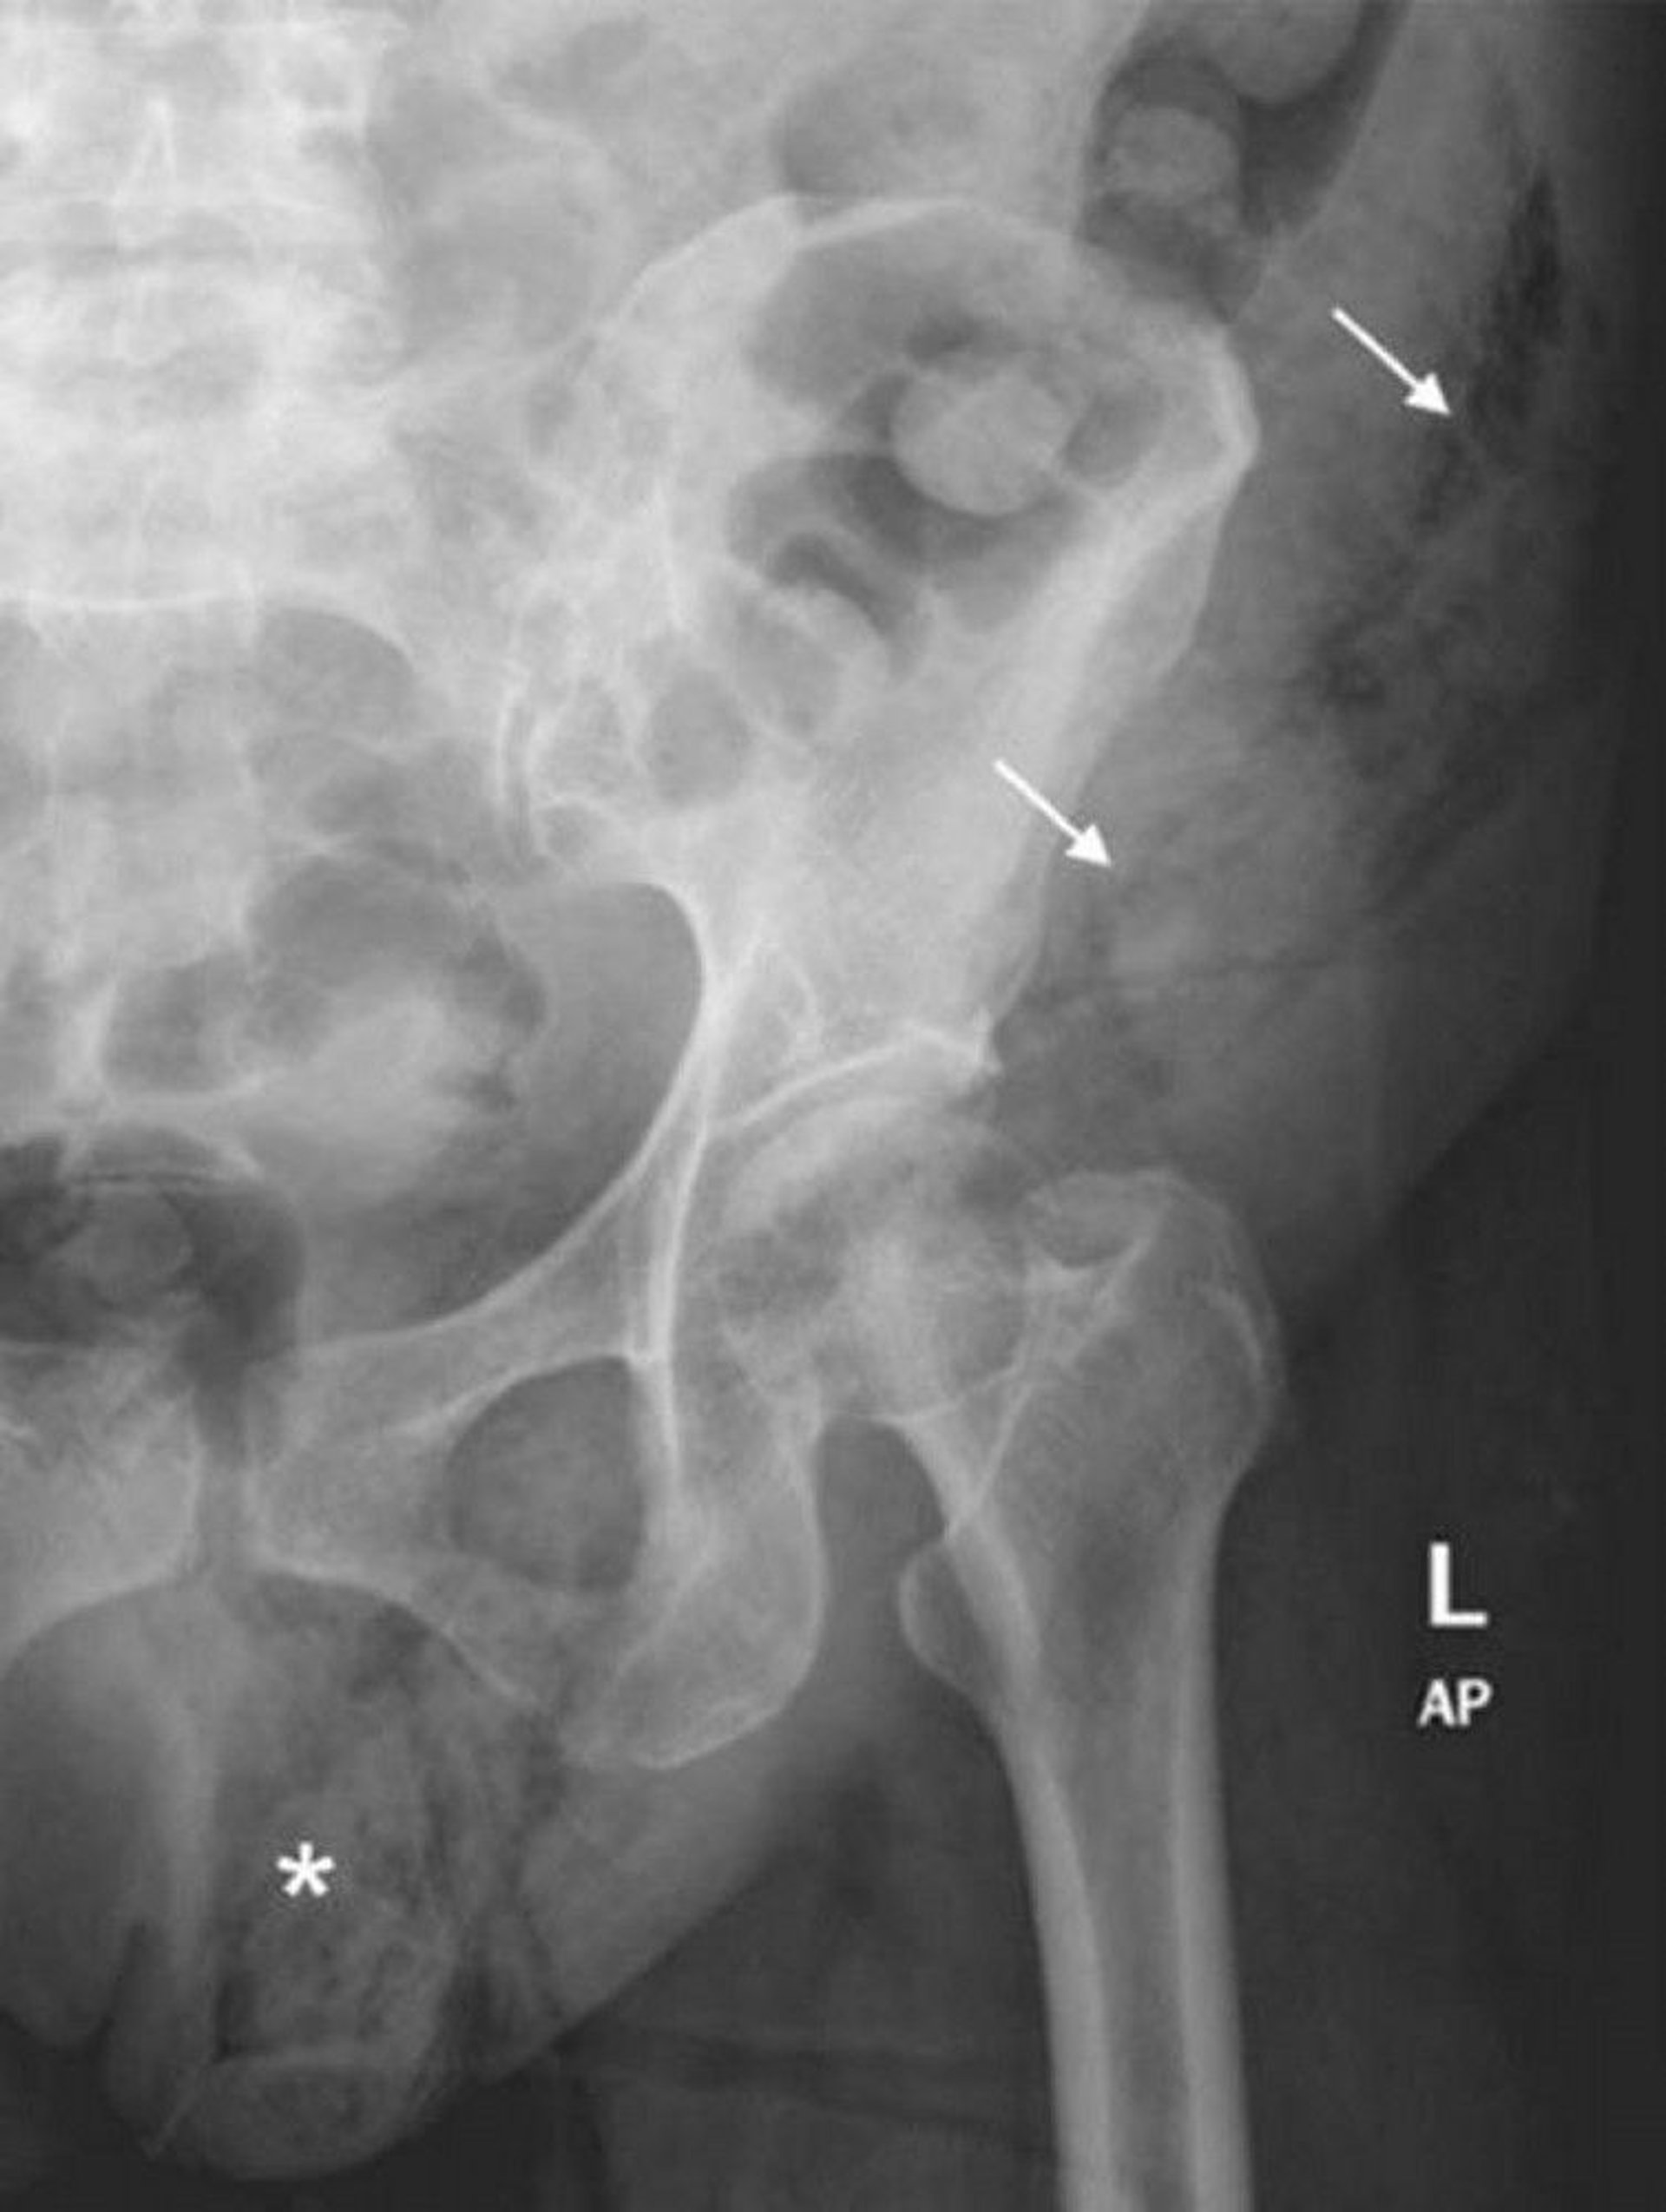

フルニエ壊疽(腹部X線)

この腹部X線写真には,左陰嚢(*)から左腹壁(矢印)にかけて軟部組織ガスが拡大している様子が写っている。